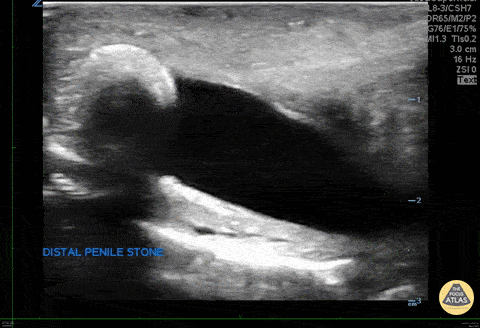

WCUME 2017 Submission and WINNER for "Creative Caption" Category "Stone in the Sword" The patient presented with penile pain and blood in urine. POCUS demonstrates a calculus obstructing the distal urethra. Inna Shniter, MD - UCI Ultrasound Fellow